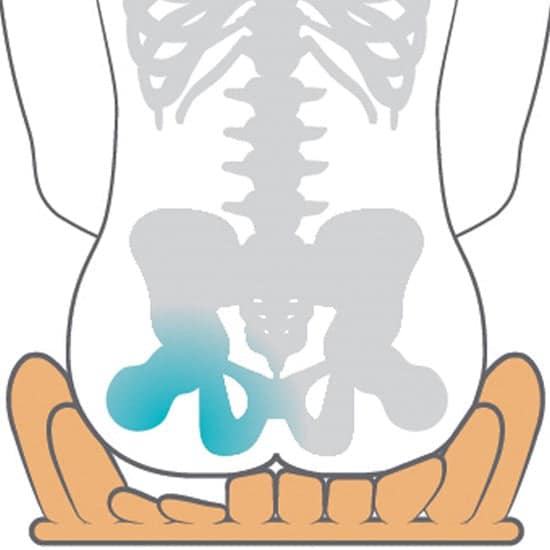

Highest Level of Therapeutic Prevention and Treatment: Provides top-tier support and care for therapeutic prevention and treatment of pressure injuries.

Outstanding Pressure Redistribution: Effectively redistributes pressure, reducing the risk of discomfort or skin-related issues.

Ultimate Immersion and Envelopment: Allows users to sink into the cushion for an immersive experience, enveloping and supporting the body effectively.